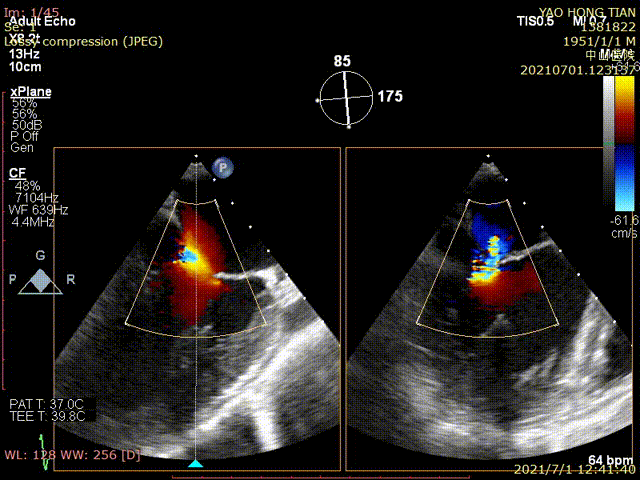

Figure 1 shows a patient's preoperative and postoperative images

Preoperative ultrasound

Postoperative ultrasound